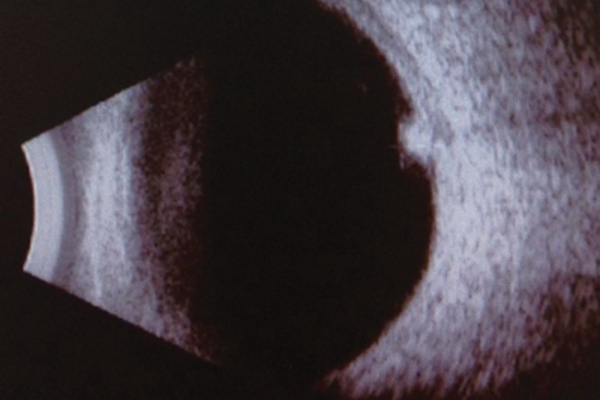

Melanocytoma of the optic disc